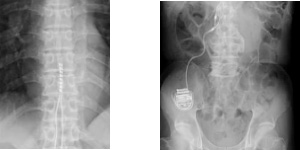

一般撮影の撮影画像

骨の画像